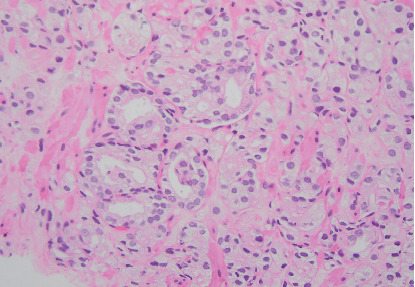

Patient selection for focal therapy (FT) of prostate cancer requires the assessment of MRI and biopsy results. However, there is currently little guidance for the utility of PSMA PET/CT in FT planning. We describe the case of a man originally considered an ideal candidate for FT based on biopsy and MRI who was found to have a contralateral lesion-harboring cancer detected only on PSMA PET/CT. Trial Registration: ClinicalTrials.gov identifier: NCT05852041.